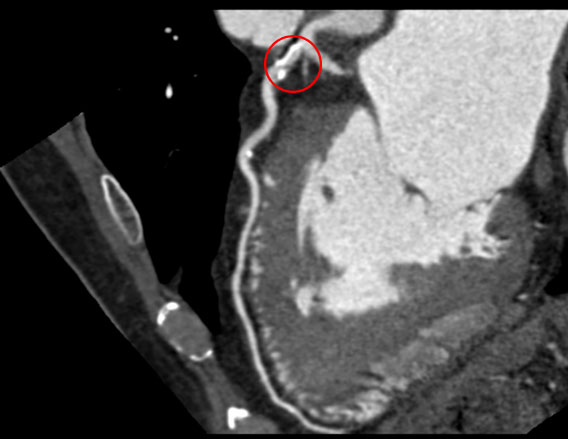

3. Bloedvaten:

Met behulp van contrastvloeistof kunnen de bloedvaten in detail worden afgebeeld. Dit is belangrijk voor de diagnose van:

- Aneurysma's: Uitstulpingen in de wand van een bloedvat, die kunnen scheuren en levensbedreigend zijn.

- Stenoses: Vernauwingen van bloedvaten, bijvoorbeeld door atherosclerose (aderverkalking).

- Trombose: Bloedstolsels in de bloedvaten, die de bloedtoevoer kunnen blokkeren.

- Longembolie: Een bloedstolsel in de longen.

- Aorta dissectie: Een scheur in de binnenwand van de aorta.